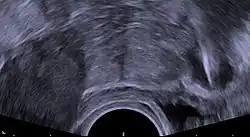

Expulsion rates can range from 2.2% to 11.4% of users from the first year to the 10th year. The TCu 380A may have lower rates of expulsion than other models, and the frameless copper IUD has a similar rate of expulsion to models with frames.[22][23] Expulsion is more likely with immediate or early postpartum or post-abortal placement.[24][25] In the postpartum period, expulsion is less likely when the device is placed less than ten minutes after the placenta is delivered, or when inserted after a cesarean delivery.[16] Unusual vaginal discharge, cramping or pain, spotting between periods, postcoital (after sex) spotting, pain during intercourse (dyspareunia), or the absence or lengthening of the strings can be signs of a possible expulsion.[21] As with intentional removal, the device is immediately ineffective after expulsion. If an IUD with copper is inserted after an expulsion has occurred, the risk of re-expulsion has been estimated in one study to be approximately one third of cases after one year.[26] Magnetic resonance imaging (MRI) may cause dislocation of a copper IUD, and it is therefore recommended to check the location of the IUD both before and after MRI.[27]

Perforation of the device through the uterine wall typically occurs at the time of placement, though it may occur spontaneously during the period of use. Estimates of the rate of perforation vary from 1.1 per 1000 to 1 per 3000 copper IUD insertions.[1][11] Perforation may be slightly more common in people using the copper IUD while breastfeeding.[28]

Due to its inflammatory mechanism of action, a copper IUD that has completely perforated typically requires surgical removal due to the formation of dense adhesions around the device. A device embedded in the uterine wall may be removed hysteroscopically or surgically.[1][16]